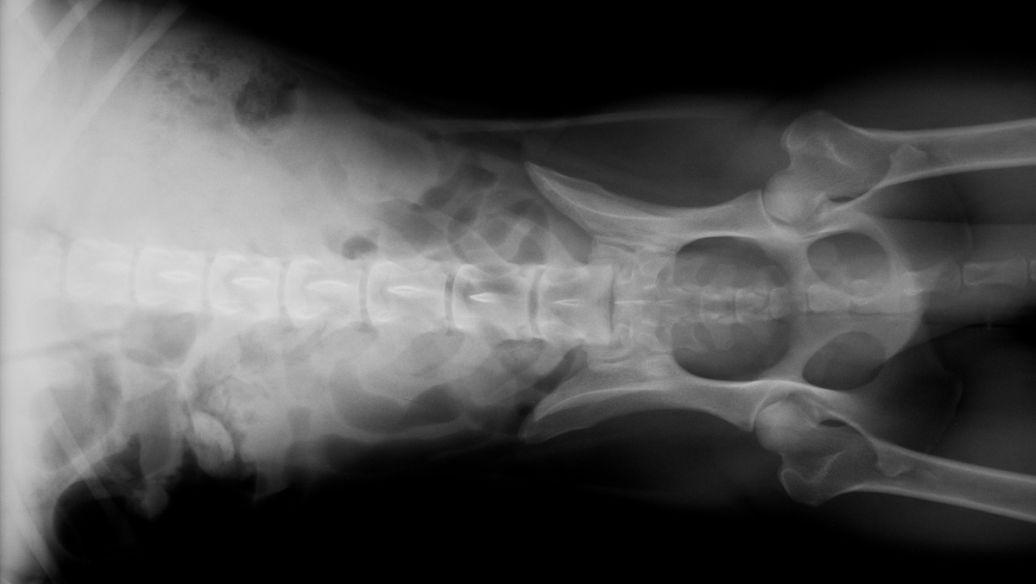

Liječenje fibrozne displazije kostiju

Fibrozna displazija kostiju je benigni razvojni poremećaj skeleta karakteriziran zamjenom koštanog tkiva abnormalnim fibroznim tkivom, što dovodi do krhkosti kostiju, boli i ograničenih mogućnosti kliničkog liječenja.Teriparatide Tabletmodulira metabolizam kostiju i potiče stvaranje normalnog koštanog tkiva, čime se poboljšavaju abnormalnosti skeleta, ublažavaju bol i poboljšavaju funkcije udova. Aktivira osteoblaste kako bi stimulirao normalno formiranje kostiju zamjenjujući abnormalno fibrozno tkivo, dok inhibira pretjeranu fibroznu proliferaciju i usporava progresiju deformiteta skeleta.